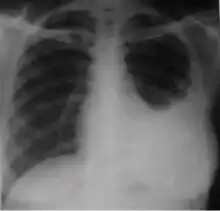

Chest x-ray showing bilateral hilar adenopathy of primary pulmonary TB